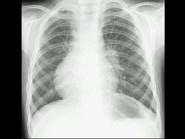

问题 男,12岁,平时无明显不适,结合图像,最可能的诊断是?(?)

选项 A.正常胸片 B.左旋心 C.右旋心 D.镜面右位心 E.以上都不是

答案 C